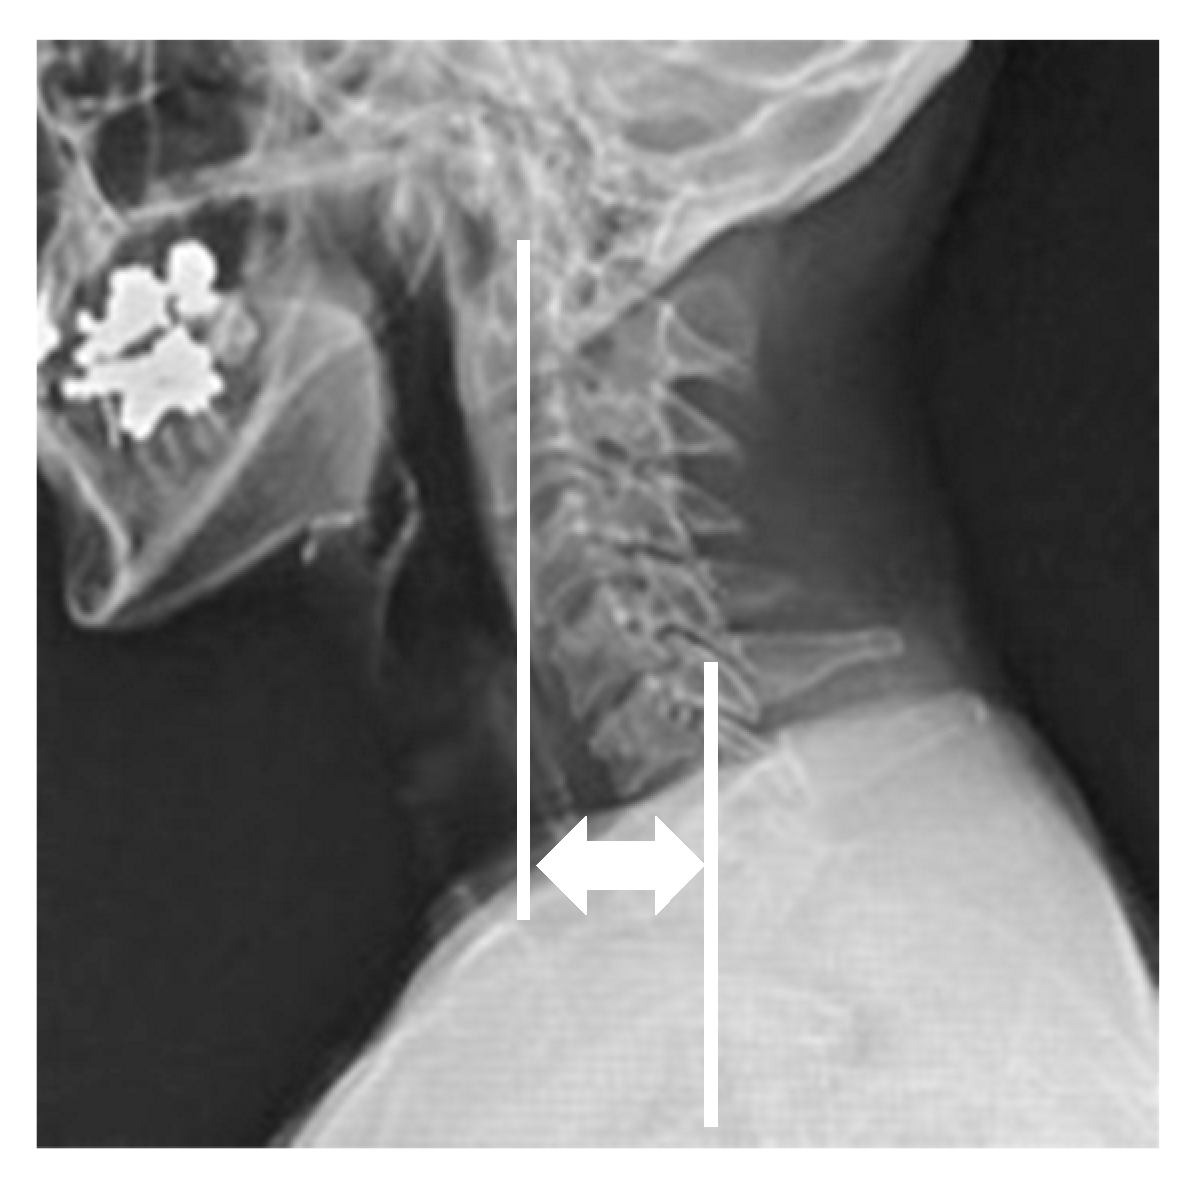

Radiographic parameters included: cervicomandibular angle (CMA) for head tilt; C2 to T1 distance for lateral shift of neck; clavicle angle for shoulder balance; central sacral vertical line (CSVL) for coronal global balance; C2–7 angles (neutral, flexion, extension) for cervical alignment and range of motion on the sagittal plane; C2–7 sagittal vertical axis (C2–7 SVA); and C7 SVA for whole spinopelvic sagittal alignment. CMA was defined as the angle between a line connecting the lower margins of the mandibular angle and the superior endplate of C7 on the anterior and posterior radiographs. The C2 to T1 distance was defined as the distance between the vertical line from the center of the C2 vertebra and that of the T1 vertebra on the anterior and posterior radiographs (Figure 1). C2–7 angles were measured by determining the C2–7 angles between the inferior endplate of C2 and the superior endplate of C7 vertebra in neutral, flexion, and extension positions on the lateral radiographs. The cervical range of motion was calculated by subtracting flexion from extension C2–7 angles. CSVL was defined as the distance between the vertical line from the midline of the sacrum and that of the C7 vertebra, and clavicle angle was defined as the angle between the horizontal line and tangential line connecting the highest two points of each clavicle on the standing anterior and posterior radiographs. C7 SVA was defined as the distance between the C7 plumb line and the posterior superior corner of the S1 vertebra, and C2–7 SVA was defined as the distance between the C2 plumb line and the posterior superior corner of the C7 vertebra on the standing lateral radiograph (Figure 2). Measurements were taken by three spine surgeons with more than 10 years of experience at our institution.

Figure 2.

Radiographic parameters; C2–7 sagittal vertical axis.

The C2–7 SVA was defined as the distance between the C2 plumb line and the posterior superior corner of the C7 vertebra on the standing whole spinopelvic radiograph (white lines).